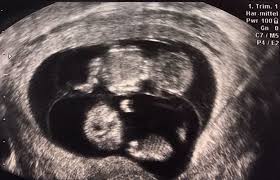

Huhuheute berichte ich euch von der 7 und der 8 WocheSo langsam fangen die Schwangerschaft Symptome an ich war in der 7 Woche zum ersten mal beim Frauenar. Frühe Zwillingsschwangerschaften im Ultraschall Eineiige Zwillinge in der 55 Schwangerschaftswoche. Wie funktioniert ein Ultraschall bei Zwillingen in der 5.

Frühe Zwillingsschwangerschaften im Ultraschall Eineiige Zwillinge in der 55 Schwangerschaftswoche. SSW ist Deine Gebärmutter so groß wie eine Faust. SSW - Ultraschall in der Schwangerschaft.

In dieser Fruchthöhle finden sich gelegentlich bereits kleine weißliche Flecken die durch die embryonalen Strukturen hervorgerufen werden. Woche SSW5 Alter 3 Wochen. In der Regel werden Zwillinge bereits bei der ersten Ultraschalluntersuchung entdeckt die etwa in der sechsten Schwangerschaftswoche erfolgt.

Die FA hat mich etwas verunsichert. Zwei Wochen später wurde dann wieder Ultraschall gemacht und da konnte man beide Herzchen schlagen sehen - Bin jetzt 285 und meine Jungs wachsen fleißig. Sicherlich haben Sie jetzt das Bedürfnis all Ihren Freundinnen und Freunden vom kleinen Geheimnis zu erzählen das da in Ihrem Bauch wächst. Wenn die Babys sich eine Plazenta teilen kann es passieren dass. Bitte um Erfahrungsberichte Zwillinge 5ssw. Sticky Post By On 4. Ihre Zwillinge in der 6. Der erste Babytragesack für Zwillinge - empfohlen von Bis -70 durch Einkaufsgemeinschaft Jetzt kostenlos anmelden kaufen Ab wann weiß ich ob die Zwillinge eineiig sind. Also seien Sie nicht überrascht sollten es Zwillinge werden aber rechnen Sie auch nicht unbedingt damit.